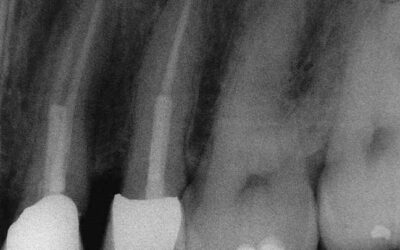

Durch Fistelung komplizierter, kombiniert endodontisch-parodontologischen Fall, wie er täglich vorkommt und genau so regelmäßig zur Extraktion gelangt. Dabei ist ein solcher Befund mit Geduld sehr einfach und routinemäßig auszuheilen.Deutlich sieht man die abgefüllte...